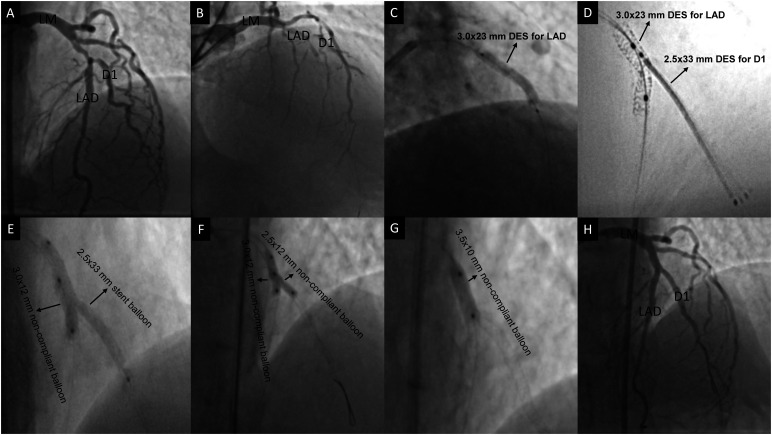

A Novel Bail-Out 2-Stent Technique for Coronary Bifurcation Disease: Reverse Controlled Balloon- Crush.

冠状动脉分叉疾病的一种新型纾困支架技术:反向控制球囊粉碎。